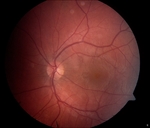

External examination was within normal limits. Visual acuity was 20/25 OD and 20/200 OS. Pupillary responses, visual fields by finger confrontation, extraocular movements, and intraocular pressures were all normal. Slit lamp examination was remarkable for mild nuclear sclerotic cataracts OU with no anterior chamber cell or flare. The vitreous was clear OU. Fundus examination revealed peripapillary atrophy, OS worse than OD, with moderate cupping of the optic discs ( Figure 1). The macula OD was flat without cystoid macular edema. A large subretinal hemorrhage was present OS. The retinal vasculature was within normal limits OU. Cobblestone changes and punched-out chorioretinal scars were seen in the periphery OU.

Optical coherence tomography revealed fibrosis and edema OS. Fluorescein angiography was performed.